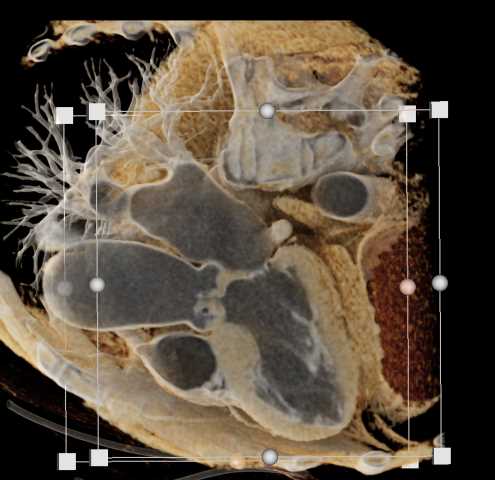

Primary Spindle Cell Carcinoma of the Right Ventricle